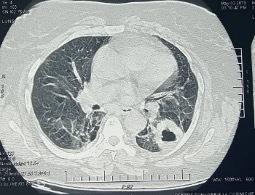

We reported the case of a 68-year-old woman with no history of chronic diseasewho presented with dyspnoea on exertion, cough and fatigue. The physical examination was unremarkable. A CT scan showed a cystic mass with a thickened wall in the apical segment of the left lower lobe. A biopsy of the mass was performed, and histological and immunohistochemical study confirmed the diagnosis of AL amyloidosis. The patient's clinical and radiological symptoms spontaneously improved without treatment after 3 years.

我们报告了一例68岁无慢性疾病史的女性病例,该患者表现为劳力性呼吸困难、咳嗽和疲劳。体格检查无异常。CT扫描显示左肺下叶尖段有一个壁增厚的囊性肿块。对该肿块进行了活检,组织学和免疫组化研究确诊为AL淀粉样变性。3年后,患者的临床和影像学症状未经治疗自行改善。